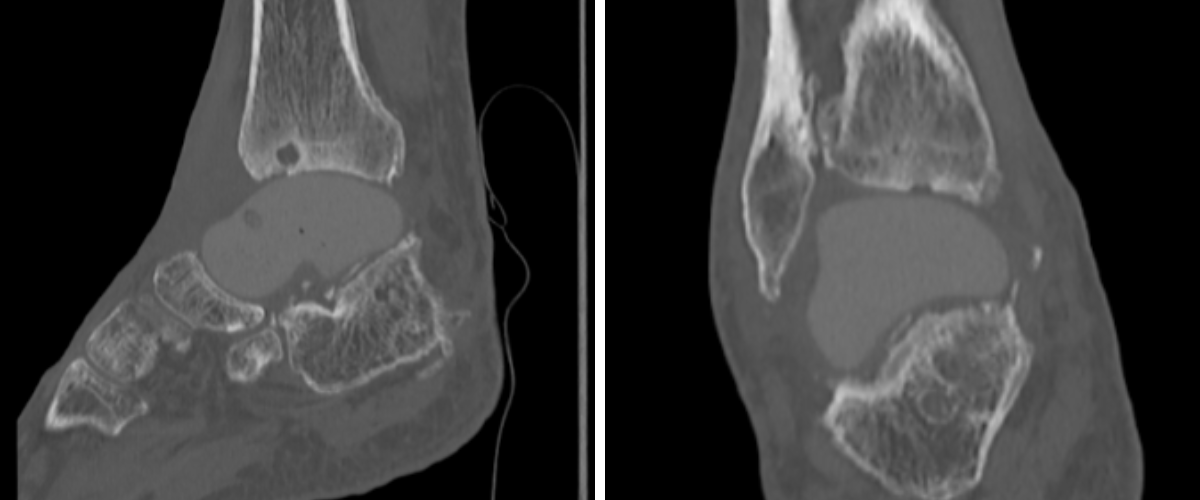

Preoperative plain film imaging demonstrated intact hardware with slight lateral deviation, implant tilt, medial tibiotalar joint space narrowing, varus deformity, and degenerative changes in both the tibiotalar and subtalar joints (Figure 1). Computed tomography (CT) confirmed subchondral sclerosis and erosive changes along the tibial plafond and subtalar articular surface (Figure 2). In addition, CT imaging of the contralateral ankle guided preoperative planning and informed patient-specific implant design. A 3D model with prototype images assisted with preoperative planning (Figure 3). The final implant was manufactured from 3D-printed PEKK by Oxford Performance Materials (OPM).